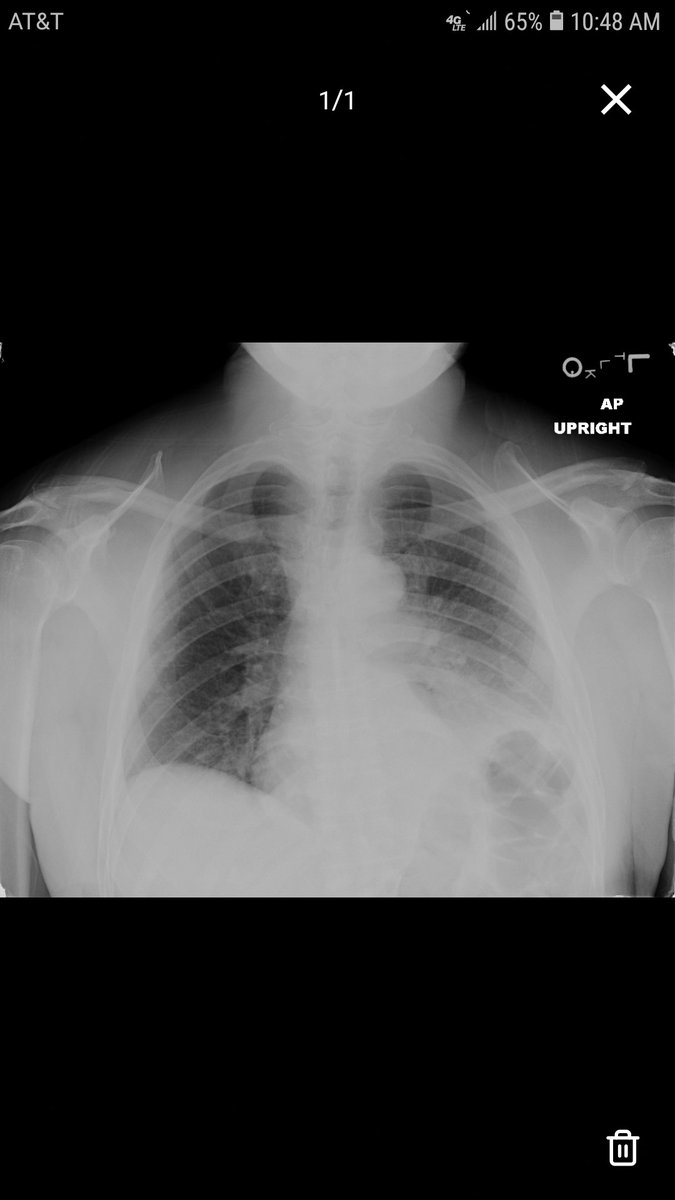

Admitted to floor, vanc + pip-tazo, continues fevering to 39.4, diarrhea improving. Liver U/S: nonspecific, acute hepatitis vs periportal edema. Stool PCR negative, blood cultures negative. Acute hepatitis panel negative. Diagnosis revealed next!